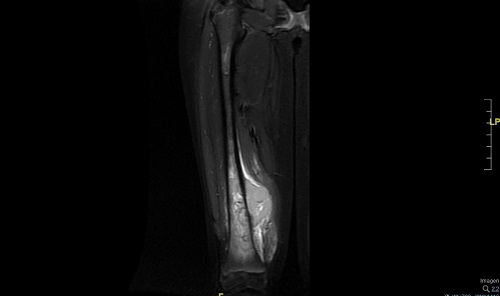

Se realiza traslado a hospital de referencia para ingreso en Unidad de Oncología. A su ingreso se amplía el estudio de la lesión realizando una resonancia magnética (Figs. 2 y 3) y estudio de extensión con tomografía computarizada pulmonar confirmándose la sospecha de tumor maligno óseo y metástasis pulmonares. Posteriormente se toma biopsia de dicha lesión guiada por ecografía confirmándose el diagnóstico de osteosarcoma.

| Figura 3. Resonancia magnética. Lesión agresiva medular ósea (10 cm de extensión cráneo-caudal) con masa de partes blandas paraostal (35 × 62 × 42 mm) que sobreeleva el periostio en fémur distal derecho |

|---|

![]() |